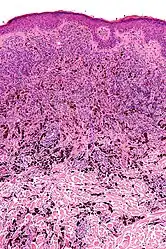

Histopathology

Micrograph of a blue nevus showing the characteristic pigmented melanocytes between bundles of collagen. H&E stain.

Micrograph of a blue nevus showing the characteristic pigmented melanocytes between bundles of collagen. H&E stain. Blue nevus